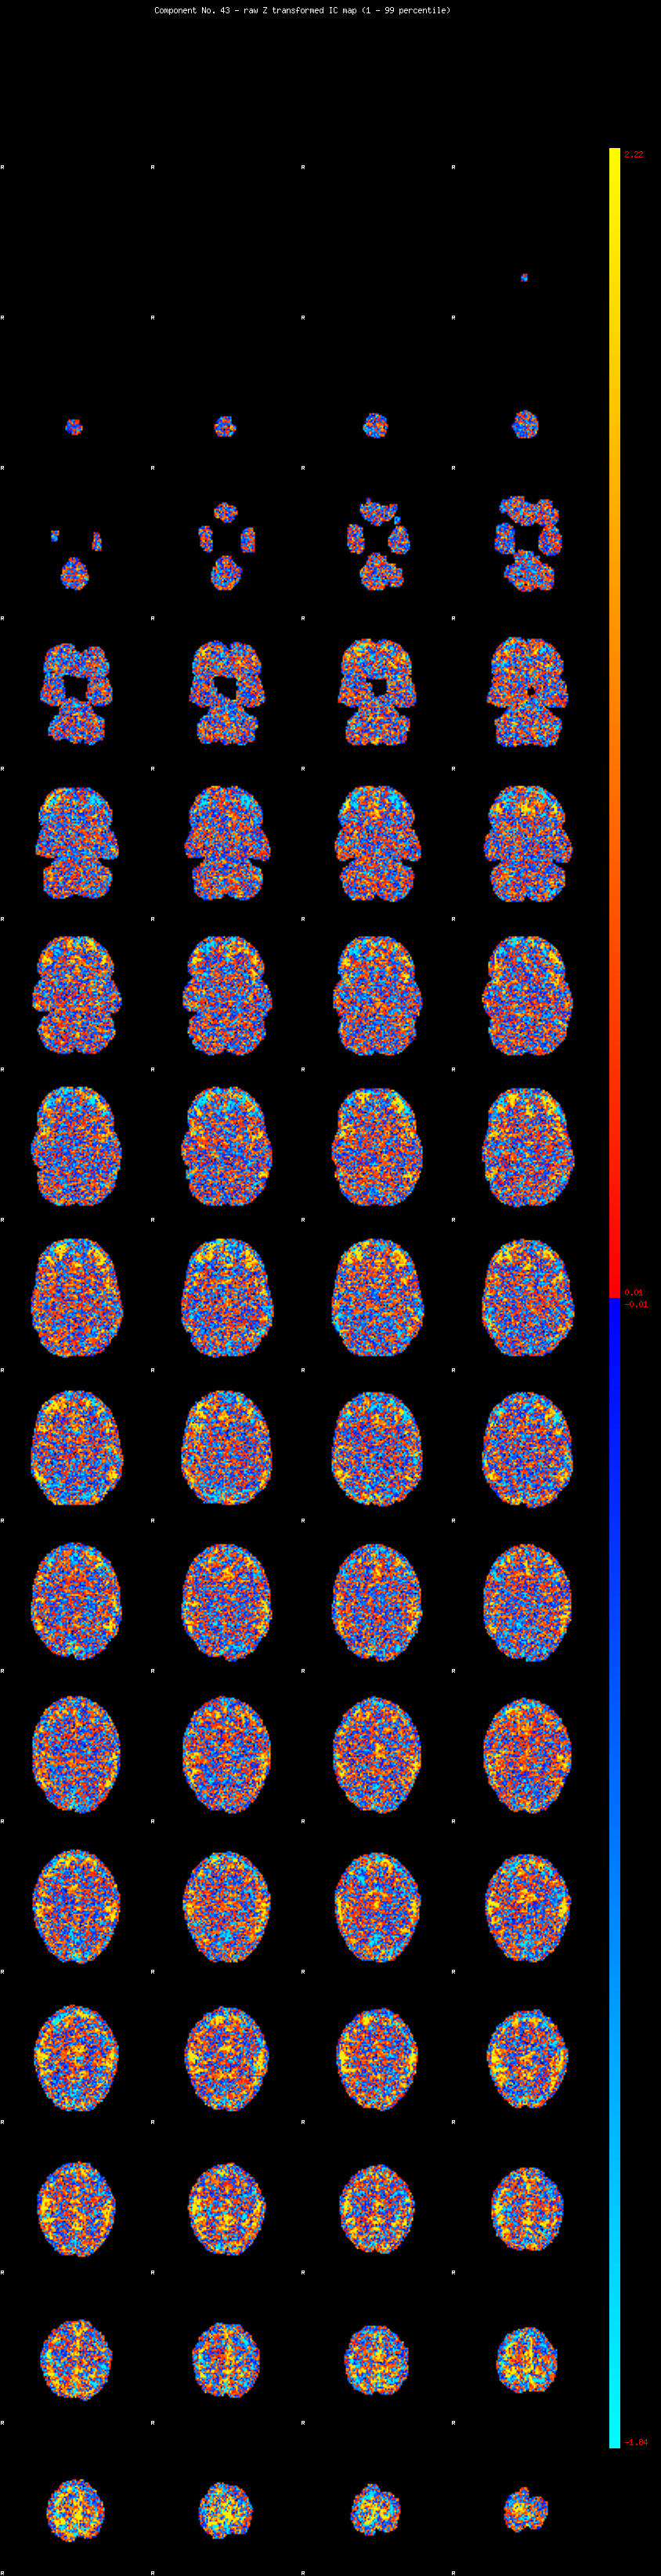

IC_43 Mixture Model fit

Means : -0.000000 2.966267 -2.735116

Vars : 1.000000 3.738987 1.511087

Prop. : 0.938599 0.046818 0.014583

This page produced automatically by MELODIC Version 3.14 - a part of FSL - FMRIB Software Library.